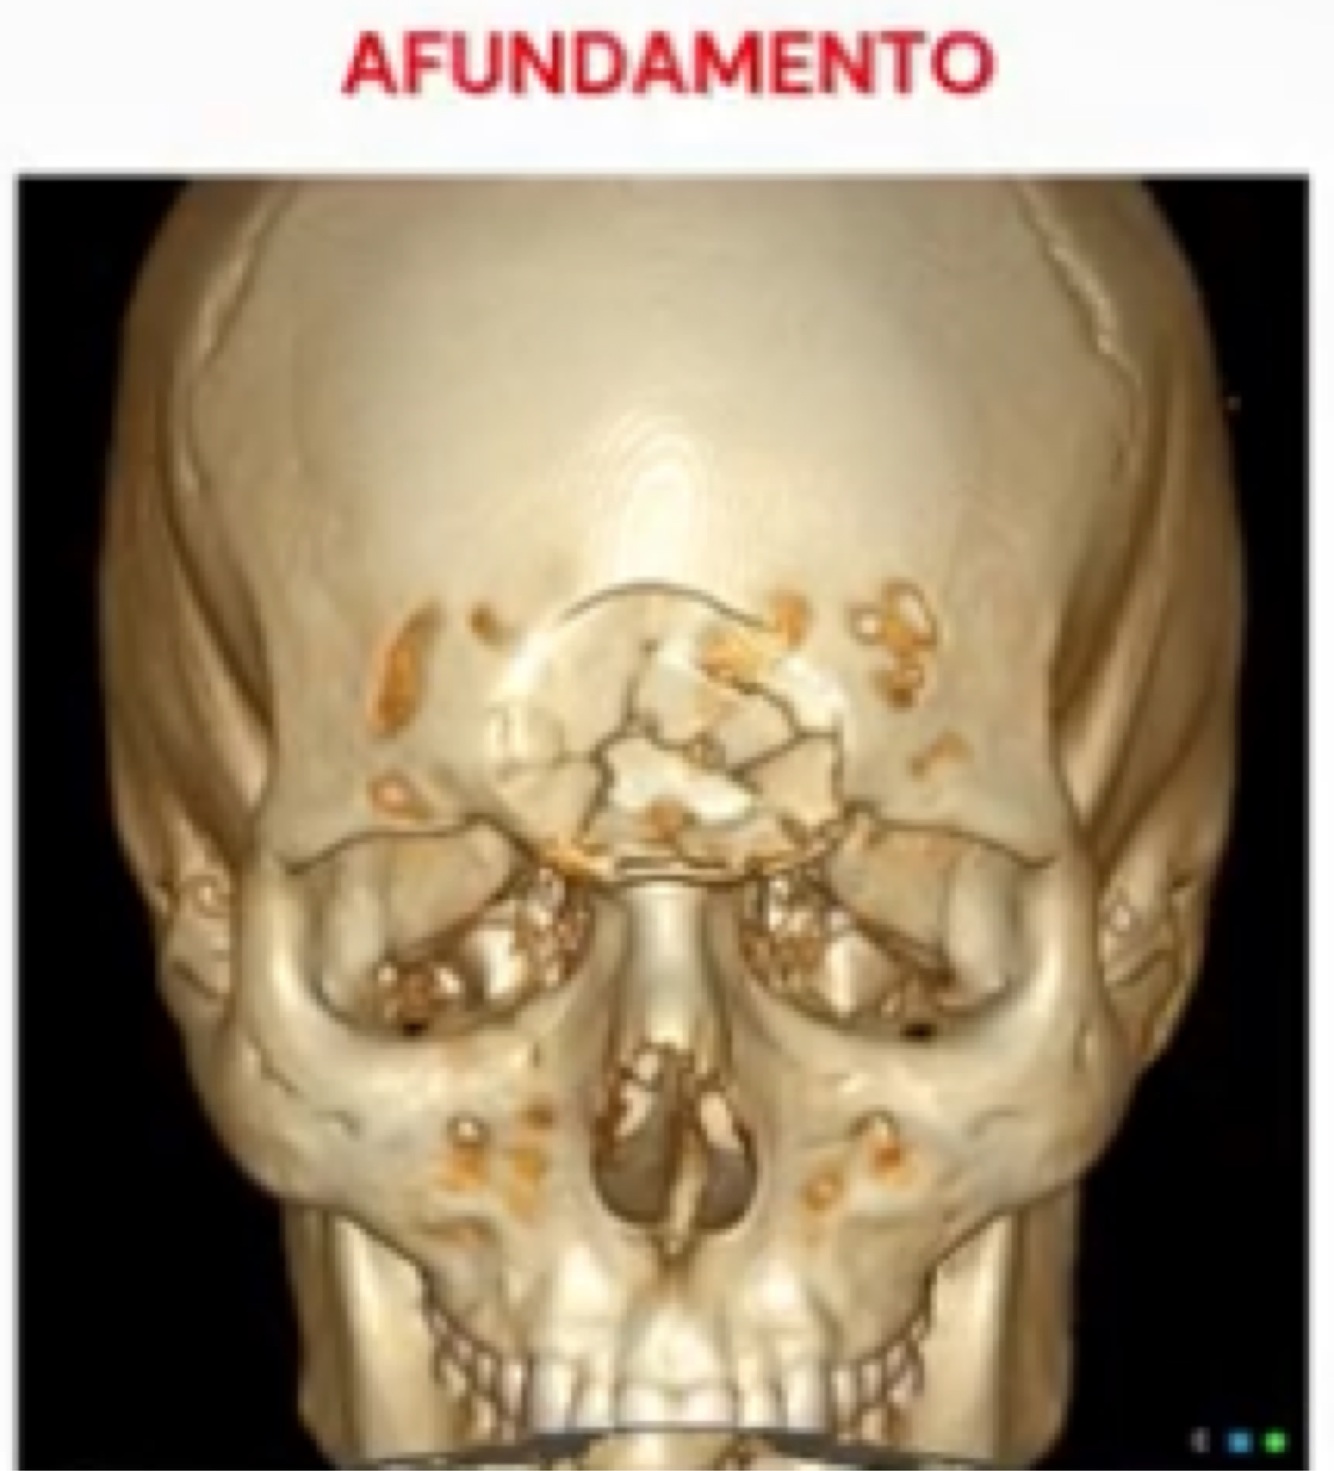

Tipo de fratura a seguir:

A